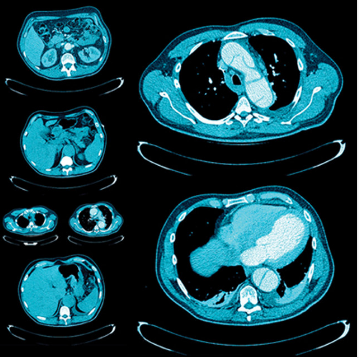

A comprehensive review of clinically relevant topics in thoracic and abdominopelvic imaging, this online video CME program lends special attention to imaging findings, reporting and management guidelines, and multimodality evaluation. Presenters — including UCSF and guest faculty — review indications commonly seen in general practice and highlight state-of-the-art imaging approaches.

Continuing medical education topics include pulmonary embolism, diffuse lung diseases, masses and malignancies of all major organs, emergent gastrointestinal conditions, multimodality evaluation of transplant donors and recipients, and more.